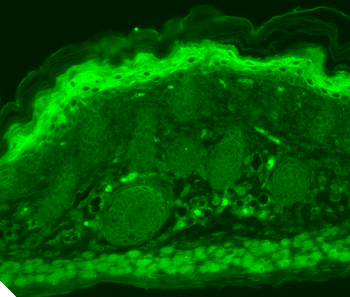

Immunofluorescence analysis of HepG2 cells using TRPV1 antibody